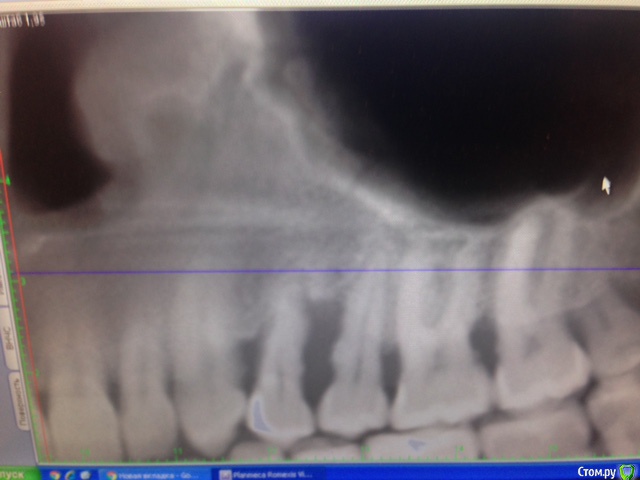

Hellae Опубликовано 17 января, 2016 Поделиться Опубликовано 17 января, 2016 Просьба откликнуться специалистов что делать в моей ситуации. У меня уже год шатается 4 зуб верхней левой челюсти. Длительное время постоянно кровил. Удалять сказали еще в феврале 2015, но я все никак не решалась т.к. вместе с ним требуется удаление еще и 5-го зуба рядом с ним. Плюс ко всему это связано с генерализованным парадонтитом(так мне сказали) на фоне которого и расшатался 4-й зуб. Сейчас имплантолог сказал надо удалить 2 зуба (4 и 5) подсадить костную ткань и ждать когда она приживется, потом ставить импланты, а пока кость нарастает сделать лоскутные операции.Снимки у мня только КТ февраль 2015 я сфотографировала панораму и прицельный двух зубов может можно как то по ним увидеть. Ссылка на комментарий